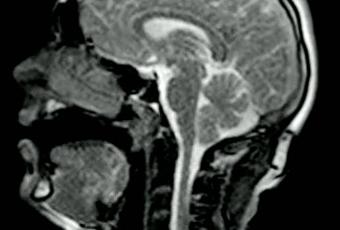

Avec sa sa chanson » Better Man than He « , le chanteur anglais SHIVU et le réalisateur Adam Powell, proposent un clip sous la forme d’une IRM (imagerie par résonance magnétique). Une expérience menée au Barts Hospital de Londres. Tout va bien docteur ? Et cette tache là en haut à droite ?